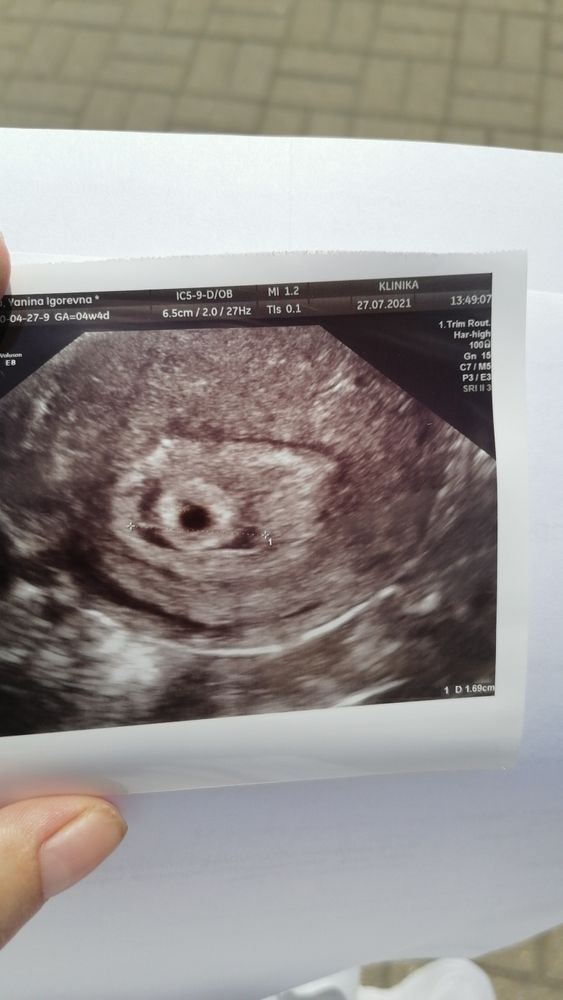

Вот, я здесь вижу Изображение

Я тоже гематомку и отслойку вижу